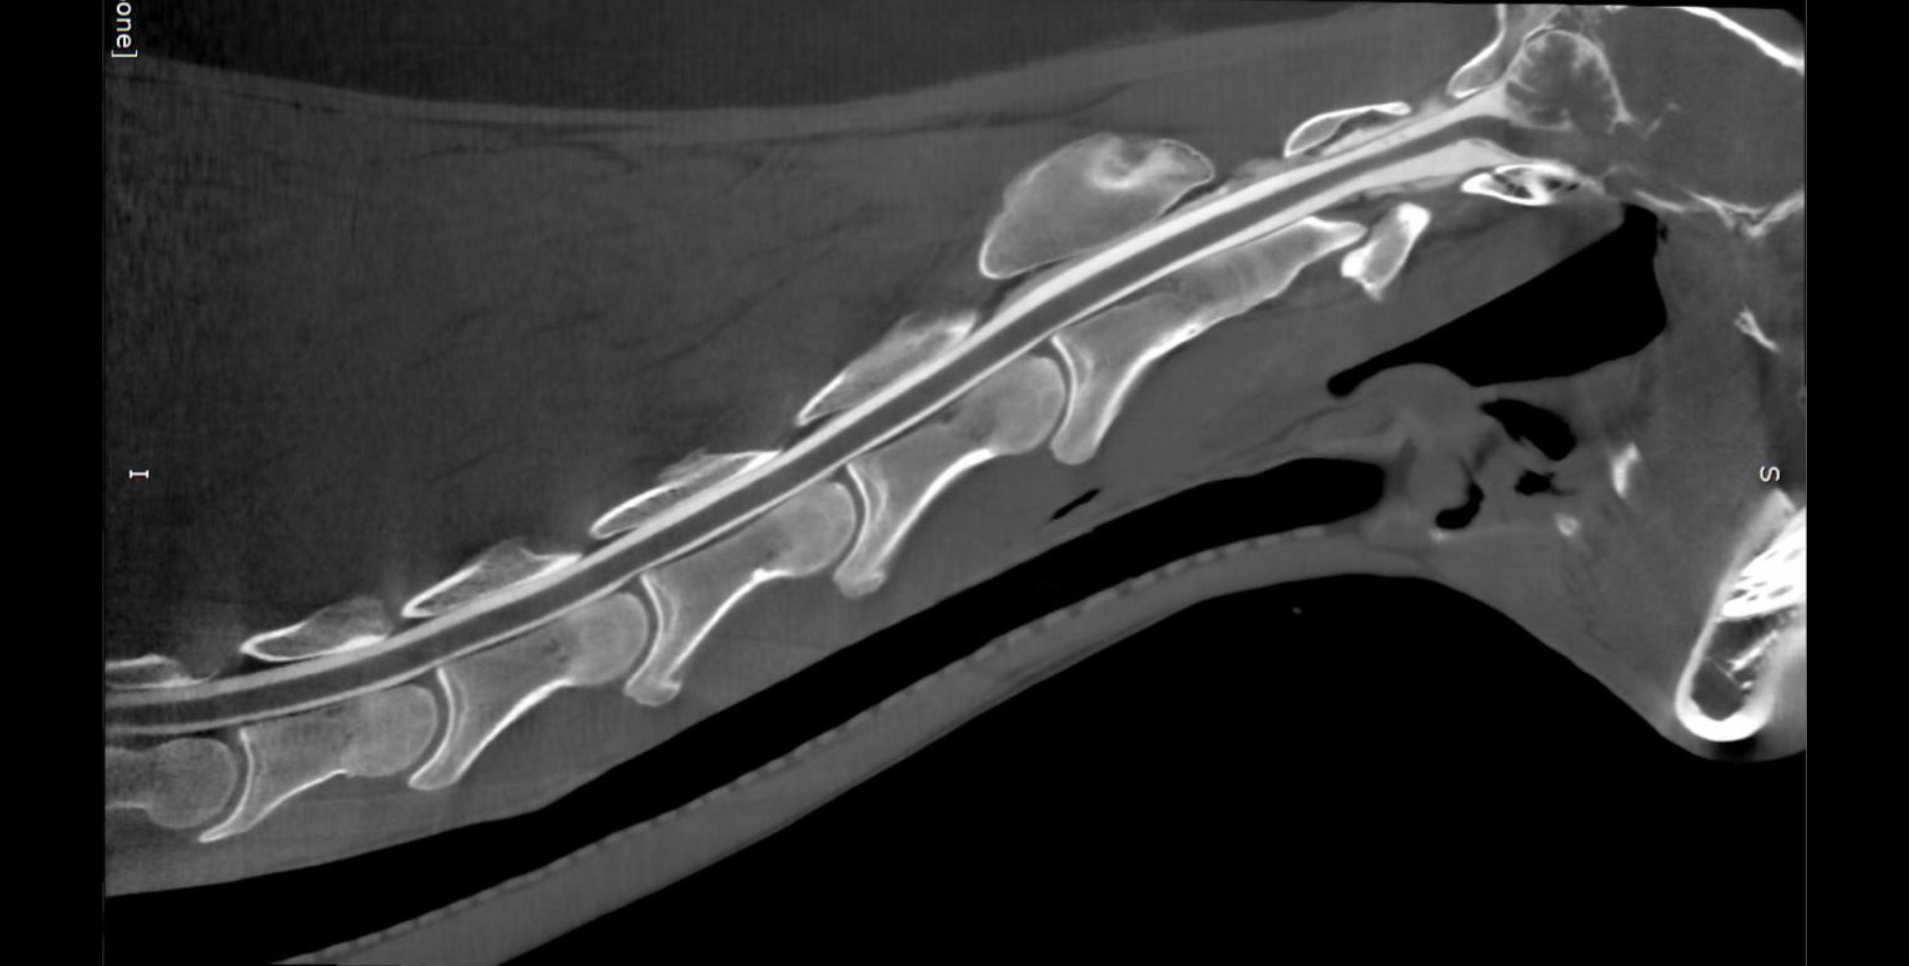

Read MoreTraditional radiographs (including a skyline view) showed subtle changes but made the fracture difficult to visualize clearly. CT imaging provided a dramatic improvement in diagnostic clarity. The scan revealed a distinct fracture line, surrounding sclerosis, and areas of demineralization features that were not easily discernible on radiographs.